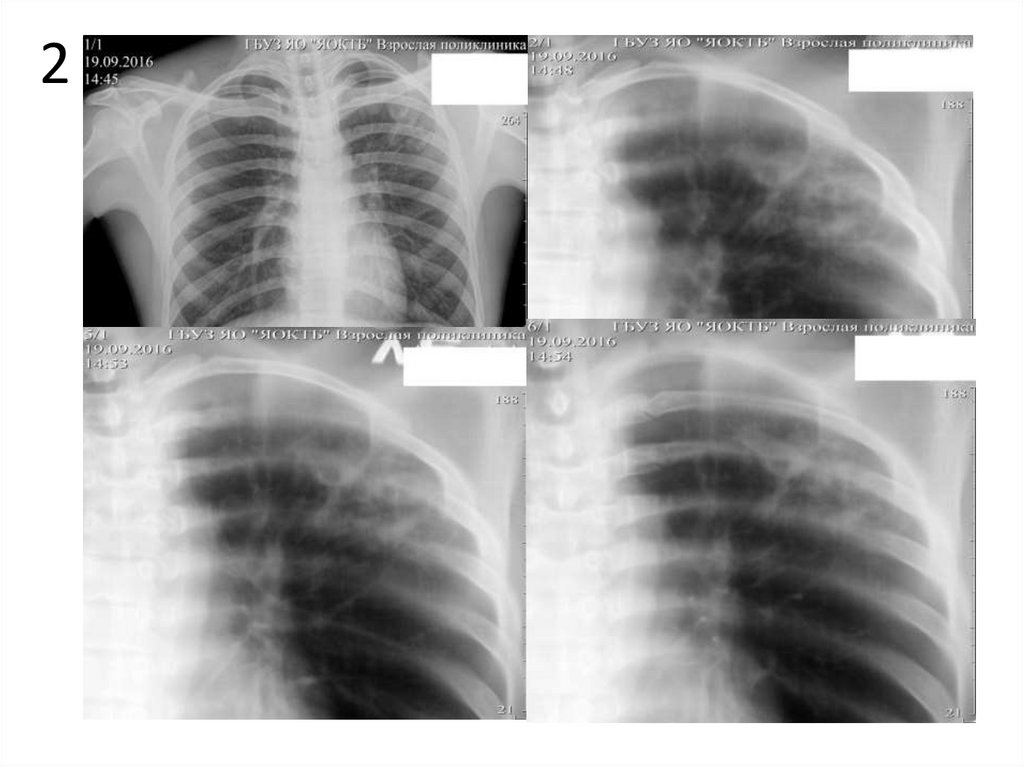

2

1. Опишите представленные снимки, выделите основной

рентгенологический синдром.

2. Имеются ли признаки туберкулеза на данных снимках?

Если да, перечислите их.

3. При наличии признаков туберкулеза определите форму,

фазу процесса, укажите возможные осложнения.